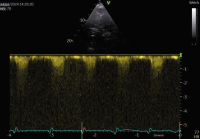

Echo

Abbildung 2: (a): Untersuchung mit der Stabsonde von rechts parasternal, Patient liegt auf der rechten Seite; (b): Aortenklappenstenose mit Stabsonde von rechts parasternal. Die VTI von apikal betrug nur 80 cm, von parasternal mit der Stabsonde 103,5 cm, was einen gravierenden Unterschied bedeutet

Keywords: AortenklappenstenoseEchoKardiologiephoto